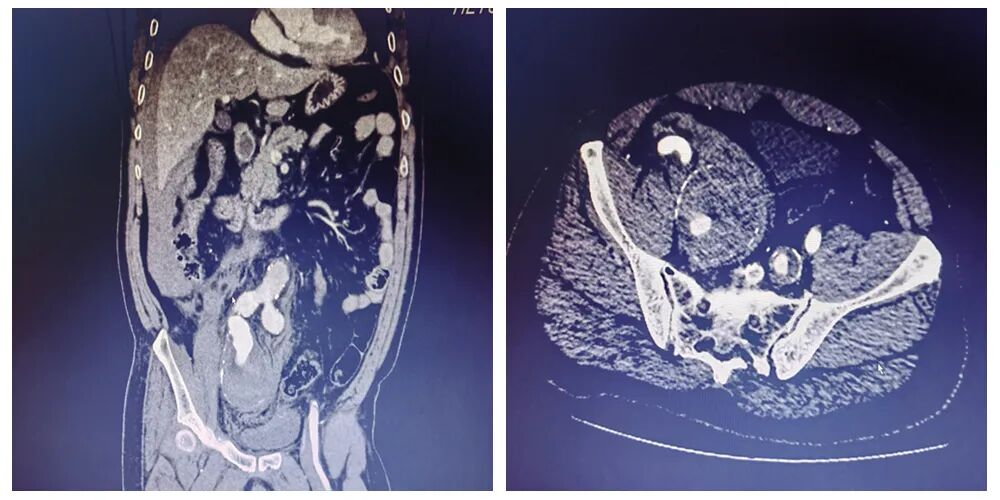

在紧张有序的筹备后,患者被迅速送入手术室。李立涛主任带领团队,凭借丰富的经验和娴熟的技术,为患者实施了“髂动脉瘤覆膜支架置入术+腹主动脉覆膜支架腔内隔绝术+髂动脉栓塞术”。手术通过股动脉穿刺点,在血管腔内精准定位、修复破口、隔绝瘤体,成功止住了致命性大出血。患者术中血压曾低至接近30mmHg,命悬一线,依赖手术团队快速的精准介入止血、麻醉医生的生命支持及护理人员的紧密配合,患者生命体征逐渐稳定。整个手术过程顺利,避免了传统开腹手术的巨大创伤,为后续康复奠定了坚实基础。

▲主动脉CTA提示右侧髂内巨大动脉瘤破裂出血